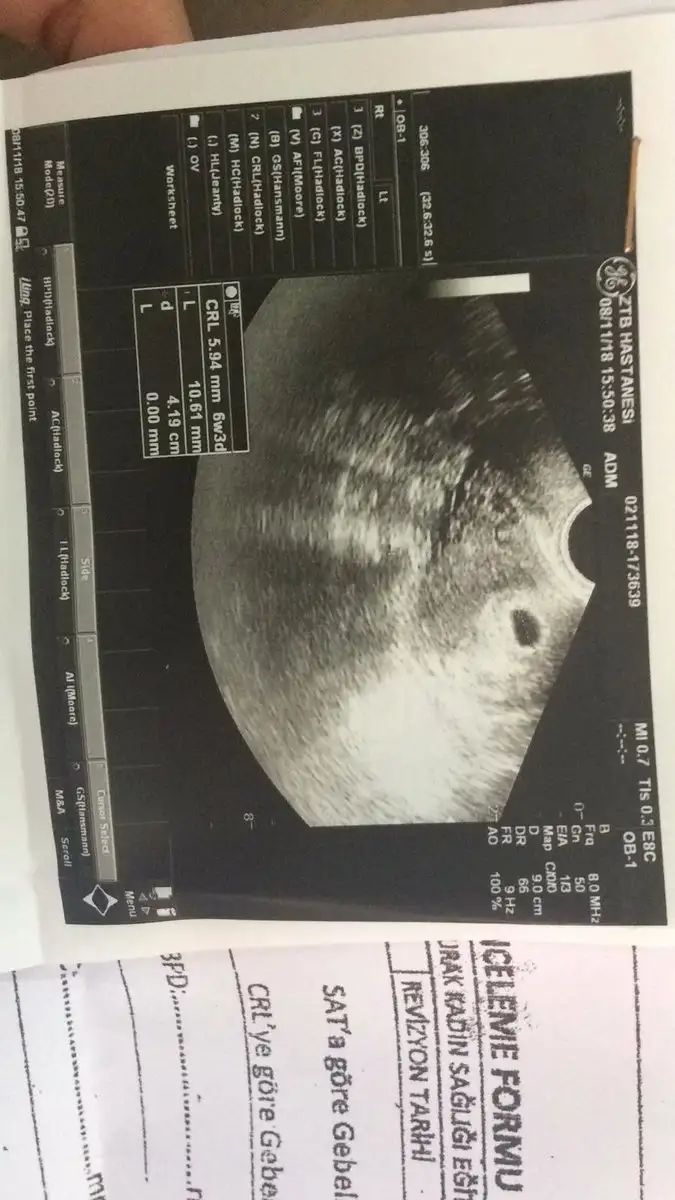

Bana da 2 hafta sonra gel dedi ama daha 5 gün geçti, sabırsızlanıyorum bir yandan da korkuyorum ya boş gebelikse diye. Ben bu hafta inanılmaz mide bulantısı yaşıyorum iştahım çok açık her şeyi yemek istiyorum ama su bile içsem midem bulanıyor. Sizin kaçıncı haftada 4 mmdi? Forumu okuyorum 5 haftalıkken keseleri 7-8 mm olanlar gebelik kesesi gelişmiyor diye üzülüyorlardı, bu durumda benim oturup ağlamam lazım herhalde. Aslında CRL ölçüsü falan yazıyo ultrason sonucunda, CRL 5.49 6w3d yazıyo ama altta elle yazdığı kısım kafamı karıştırıyor işte.

Ben haftaya pazartesi yine gideyim 10 gün daha bekleyemicem. Kalp atışlarını duyamasam da büyümesi düzenli mi onu öğrenirim hiç olmazsa. Foto ekledim, bu görüntü geçen perşembe gününün 5+6 günlük yani. Sorun var mı sizce?

Eki Görüntüle 2205534 Eki Görüntüle 2205535

yolk kesesi saptayamamış çünkü henüz çok küçük görünmez

embriyo zaten görünmez

kese yukarda gayet iyi hiç kafana takacağın bişey yok canım haftaya git bebeğini bile ölçer rahat olsun kafan